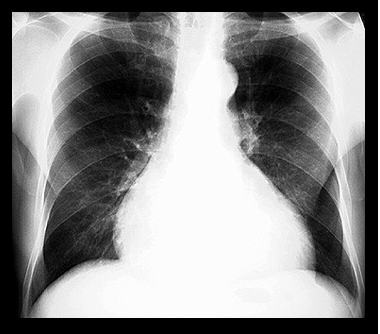

HIPERTROFIILE

HIPERTROFIILE In anumite conditii hemodinamice, inima este suprasolicitata sa lucreze cu o cantitate crescuta de sange (insuficiente valvulare, defecte septale) sau sa lucreze contra unei rezistente (stenoze valvulare, hipertensiune arteriala).Citeste tot ... 1223 cuvinte

Dimensiune mica + cu imagini |